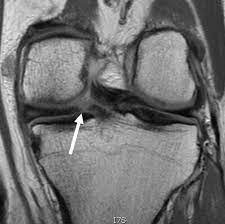

Meniscus Tear (Medial Meniscus)

Cause

Twisting or rotating the knee forcefully, such as during sports activities or heavy lifting. Degenerative tears can occur with age-related wear.

Symptoms

• Pain during movement or weight-bearing, especially when twisting the knee.

• Swelling that develops over several hours or the next day.

• Clicking, locking, or catching sensation in the knee.

• Stiffness or inability to fully straighten the knee.

• Pain may increase with stairs, squats, or deep bending.